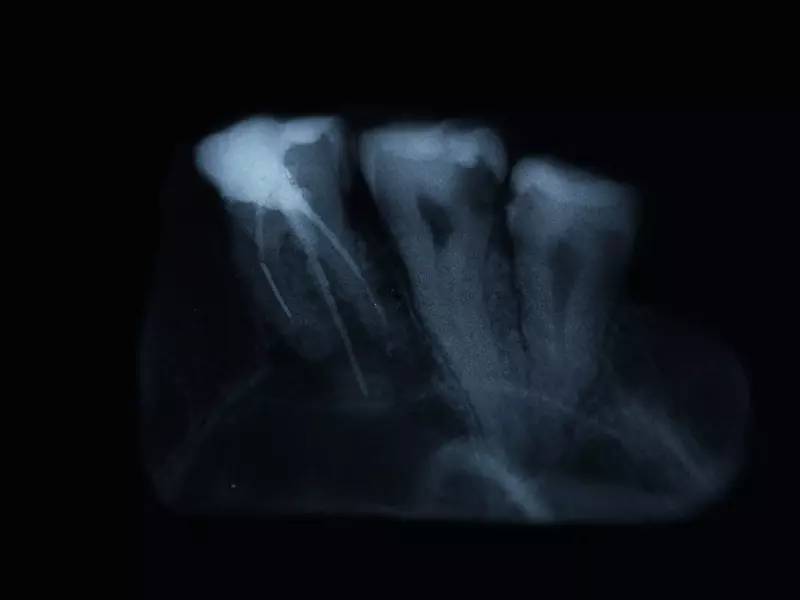

Według Paradowskiej-Stolarz i wsp. diagnostyka zęba zatrzymanego powinna obejmować zarówno badanie kliniczne (brak wyrżnięcia się zęba w odpowiednim dla niego czasie), jak i badanie radiologiczne. Autorzy podkreślają, że badaniem przesiewowym w tym przypadku jest zdjęcie pantomograficzne, jednak do pełnej diagnostyki niezbędne jest wykonanie tomografii komputerowej. Dopiero taka projekcja dostarcza pełnej informacji dotyczącej usytuowania zęba zatrzymanego oraz umożliwia zobrazowanie sąsiadujących z nim struktur, a także umożliwia zaplanowanie zabiegu chirurgicznego.

Przed przystąpieniem do zabiegu odsłonięcia korony zęba 13. wykonano znieczulenie nasiękowe operowanej okolicy (Mepidont 3% 0,5 ml).

Ustawienia pracy lasera były następujące: moc – 5 W, tryb pracy – impulsowy, odstęp między impulsami – 200 μs, czas trwania impulsu – 50 μs, moc średnia – 1 W. W trakcie zabiegu wykorzystano światłowód o średnicy 400 nm. Odsłonięto ok. 1/2 powierzchni korony zęba 13.

W kolejnym etapie usunięto ząb mleczny – 53. W celu utrzymania suchości pola operacyjnego ranę zabezpieczono materiałem hemostatycznym (Spongostan). Cała procedura trwała około 10 min. Dzięki otrzymaniu homeostazy przy użyciu lasera możliwe było natychmiastowe obciążenie zęba 13. łańcuszkiem ortodontycznym podłączonym do głównego łuku aparatu stałego.